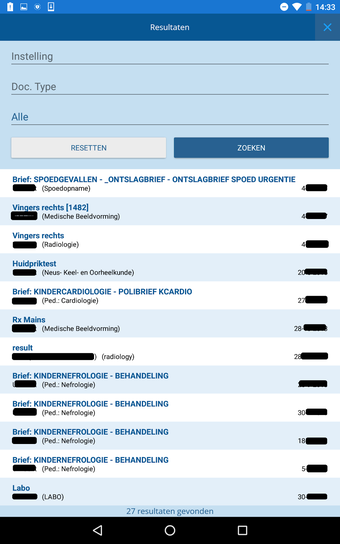

CoZo permet aux patients de prendre une part active dans leur propre santé et d'être traités comme des participants actifs dans le processus de soins. Les patients peuvent utiliser l'application pour enregistrer leurs données de santé, qu'ils peuvent ensuite partager avec leurs médecins. Les médecins peuvent utiliser l'application pour enregistrer l'historique médical de leurs patients, poser un diagnostic et suggérer un plan de traitement.